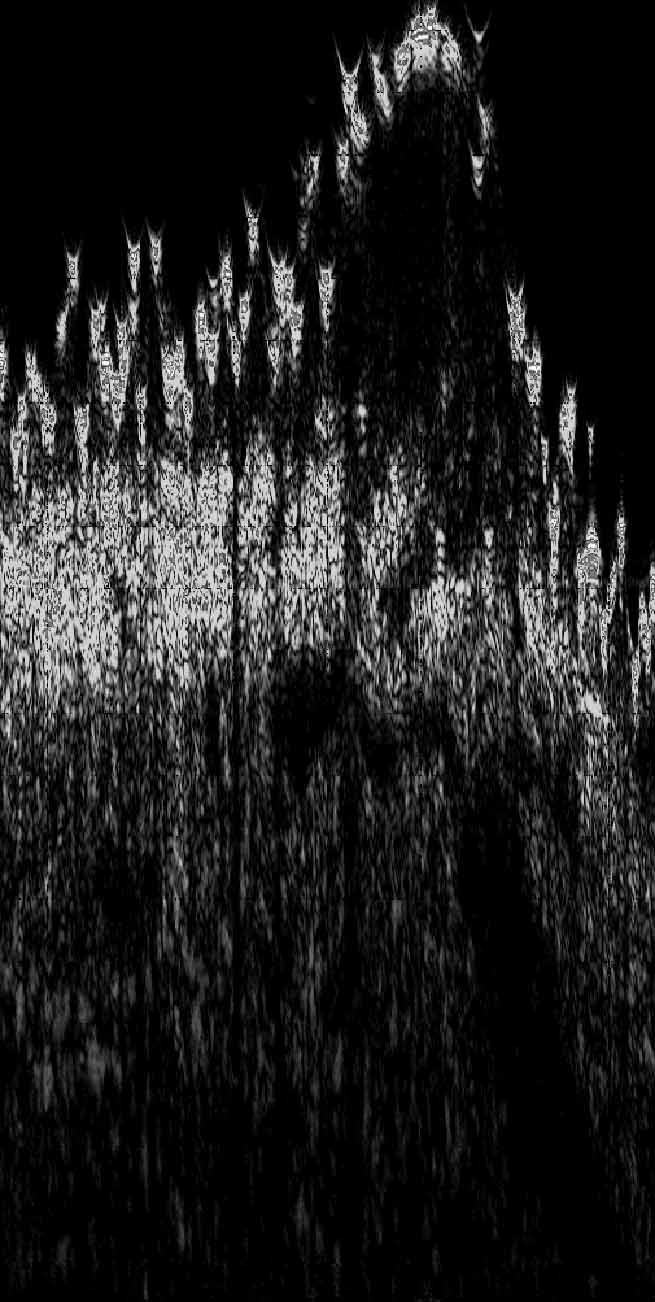

Figure 1 shows a sonogram of a mild rash of scabies disease.

Figure 1

One can see the burrows under a thin layer of stratum corneum.

The diameter of the burrows were 0.1 mm to 0.2 mm.

One can see also a higher echodensity in the burrow, especially in the enlargement. We think that this represents the fecal scybala, because an inflammation would be echopoor.

The echopoor band under the skin entry echo represents the epidermis, the papillary dermis and actinic elastosis in the upper dermis. The patient was over 70 years old.